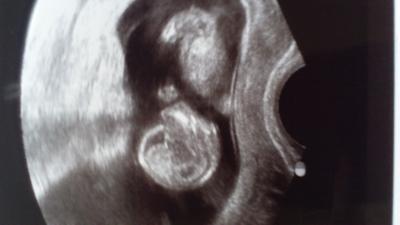

Huhu :-D Ich bin so Happy und so verliebt die kleine ist schon 6cm groß und hat wie wild gestrampelt, so schön!vor weg, ist alles in bester Ordnung! Freu* Jaaa dann die Frage alles fragen: könnte man schon sehen was es wird? Die Ärztin schaute direkt nach und stellte kurz auf 3D um! Ja Frau V. Da sehe ich definitiv Schamlippen wir können jetzt wetten das es ein Mädchen wird lach* nein, ich brauch nicht wetten und schließe mich dann mal direkt an, da ich diese auch direkt sehen konnte! Der Hammer, mein Gefühl hatte also recht WIR KRIEGEN ZU 90% EINE PRINZESSIN muahhhh. Wir freuen uns so, sind aber trotzdem noch etwas skeptisch da es nun wirklich noch sehr früh is,aber die Ärztin hätte sich wohl noch nie vertan ;-) jaja mal sehen, :-D salut die überglückliche Sally die morgen in nie 13 ssw kugelt

Oh wenn ich das Bildchen sehe wird mir wieder ganz warm uns Herz, sie hat so eine süße stupsnase